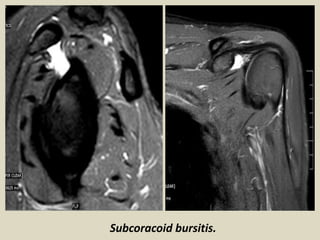

Subcoracoid bursitis.